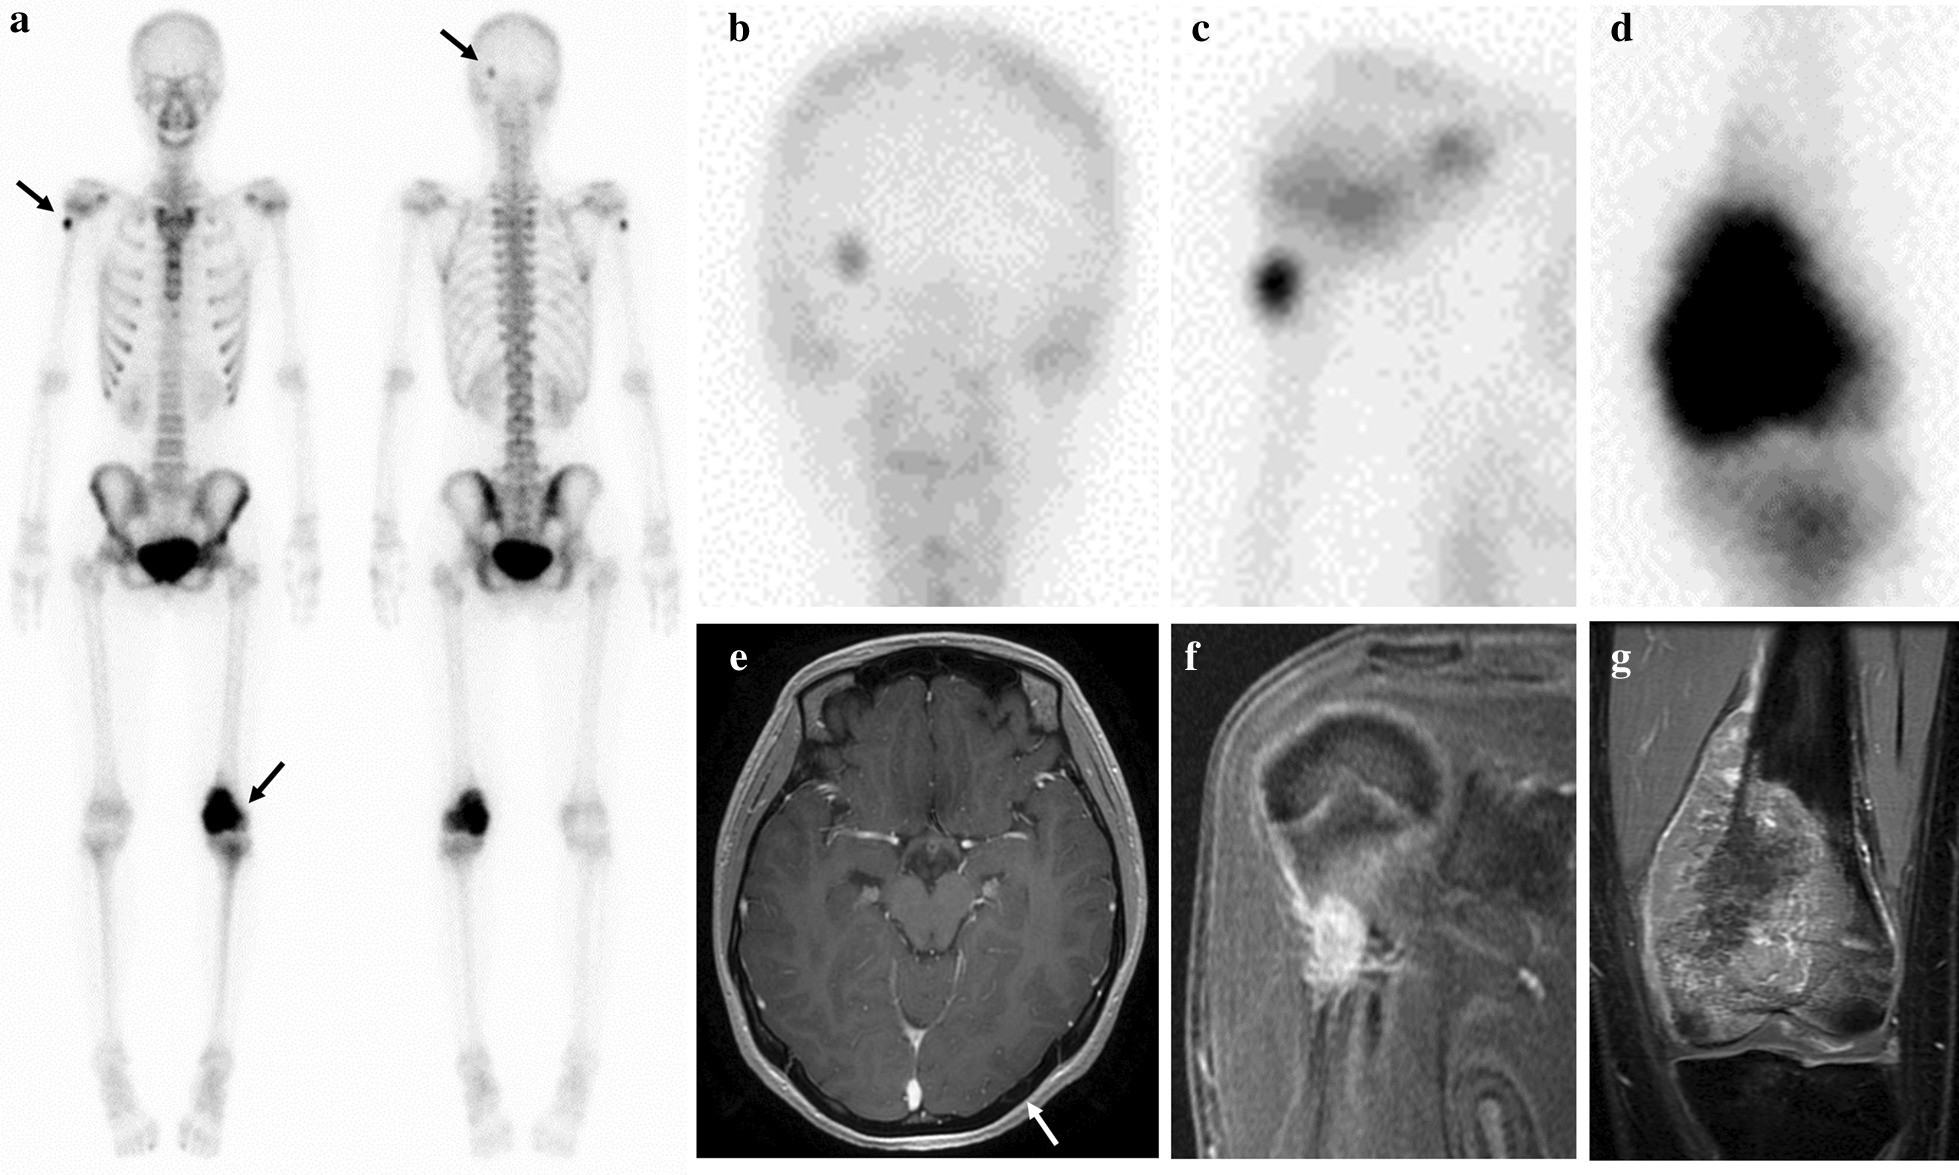

Fig. 3

Systemic bone scan and MRI findings before neoadjuvant chemotherapy. a–c Bone scan revealed uptake for the following three location (a); left occipital bone (b), right proximal humerus (c), and left distal femur (d). e The left occipital lesion on axial enhanced MRI, and a white arrow shows the intracortical lesion. f The right proximal humeral lesion on coronal enhanced MRI. g The left distal femoral lesion on coronal enhanced MRI